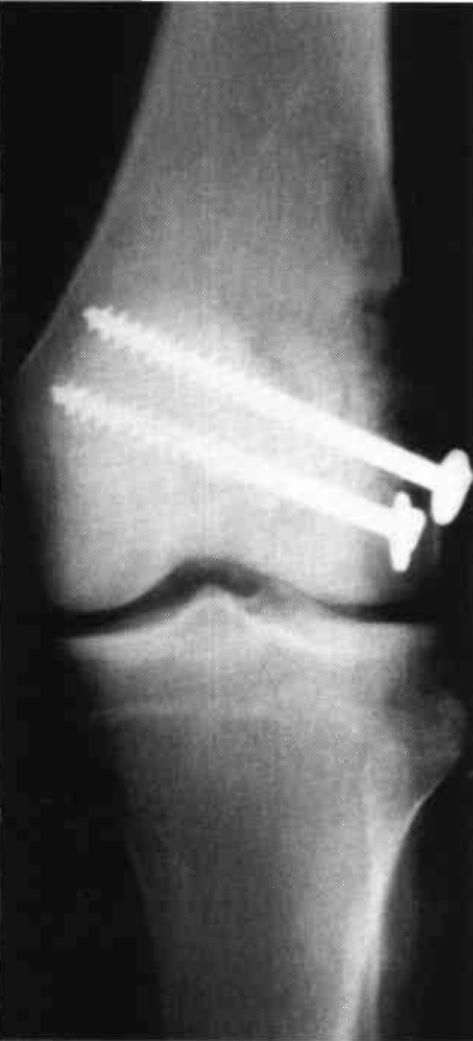

An eighteen year old male sustained bilateral femur fractures and bilateral patella fractures. The patient underwent bilateral closed inter-medullary (IM) rodding of the femur and the patellas underwent bilateral ORIF (Fig. 15 and Fig. 16). The patient was placed in a free knee Mobilizing Brace on the left leg and attached to a continuous passive motion dynamic suspension system immediately postoperatively. The right leg was maintained in a straight position and in a denotation boot to prevent the fractured femur from spinning on the IM rod. In two days, the left knee had 0-90° of pain free passive motion. Active motion on the right lower extremity was limited to 0-15° of motion. At that time, the patient's right leg was placed in a free knee Mobilizing Brace and bilateral passive motion begun (Fig. 17). Right leg motion progressed to 0-90° passive motion in four days, while the left leg was maintained in the 0-90° range. (This passive motion device, providing bilateral application from one power source, can be adjusted for varying degrees of motion independent of each other by varying the tension on the attachment lines.) Ambulation training began utilizing the bilateral Mobilizing Braces with drop locks in position (Fig. 18). The patient was fully ambulatory with this system, achieved full range of active motion in ten days, and was discharged. Passive motion was maintained for a longer period than normal due to the degree of articular damage to the patellas.

Figure 15:

Figure 16: